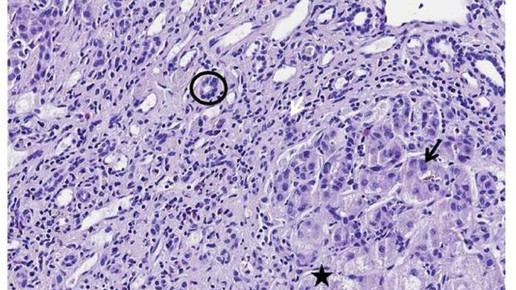

Weitere Analysen ergaben, dass die Verbesserung auf einen starken Rückgang der Kupfermengen zurück zu führen war. Speziell die als Mitochondrien bekannten „Kraftwerke der Zellen“ profitierten stark von der sinkenden Kupferlast und konnten ihre Funktion wieder voll aufnehmen. Methanobactin verhinderte ein Absterben von Leberzellen und beugte einem Leberversagen vor.

Bei der Kupferspeicherkrankheit ist der Körper nicht mehr in der Lage, überschüssiges Kupfer aus der Nahrung über die Galle in den Darm auszuscheiden. Stattdessen lagert Kupfer sich in der Leber und anderen Organen ab und kann dort schwerste Schäden verursachen.

Im Gegensatz zu der herkömmlichen Therapie konnte Methanobactin auch in Stadien schwerer Schädigung innerhalb weniger Tage die Kupferüberlastung der Leberzellen beseitigen und ein Organversagen verhindern. Zudem war der Wirkstoff im Modell sehr gut verträglich.